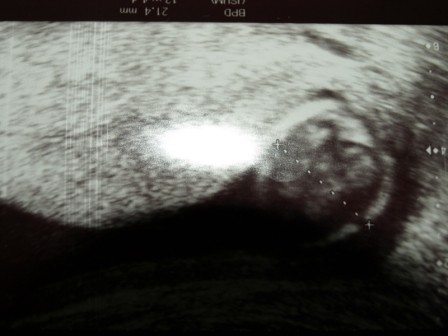

-czwarte od lewej-pomiar główki,